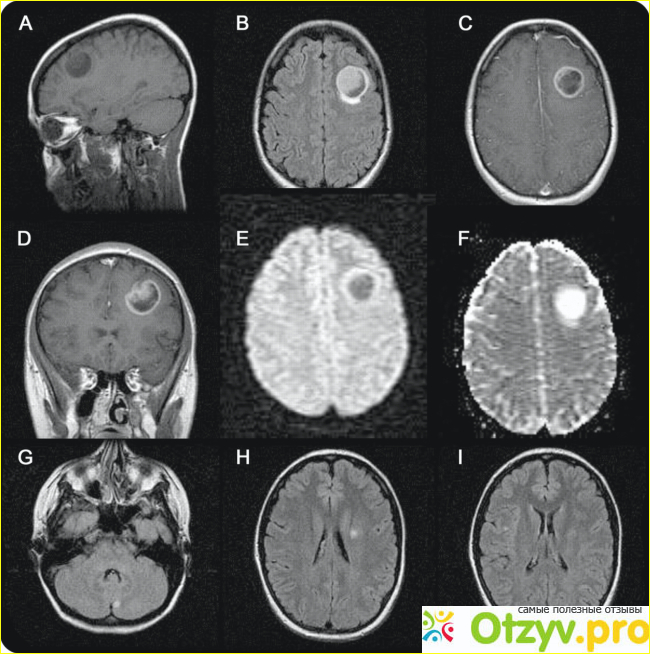

Магнитно-резонансная томография (МРТ) нервной системы использует магнитные поля и радиоволны для получения высококачественных двумерных или трехмерных изображений структур нервной системы без использования ионизирующего излучения (рентгеновских лучей) или радиоактивных индикаторов.

Для визуализации нервной системы можно использовать ряд различных способов или последовательностей визуализации:

T1-взвешенные (T1W) изображения: спинномозговая жидкость темная. T1-взвешенные изображения полезны для визуализации нормальной анатомии.

T2-взвешенные (T2W) изображения: CSF светлый, но жир (и, следовательно, белое вещество) темнее, чем с T1. T2-взвешенные изображения полезны для визуализации патологии.

Диффузно-взвешенные изображения (DWI): DWI использует диффузию молекул воды для создания контраста в МР-изображениях.

Изображения с протонной плотностью (PD): в CSF относительно высокий уровень протонов, благодаря чему CSF выглядит ярким. Серое вещество ярче белого.

Восстановление обратного затухания жидкости (FLAIR): полезно для оценки бляшек белого вещества вблизи желудочков. Это полезно при идентификации демиелинизации.

Как и КТ, МРТ позволяет вашему врачу видеть ваше тело узкими кусочками, каждый толщиной около четверти дюйма. Например, представьте, что вы нарезаете кусок хлеба и фотографируете каждый кусочек. Он может просматривать срезы снизу (осевой), спереди (корональный) или сбоку (сагиттальный), в зависимости от того, что должен видеть ваш врач.